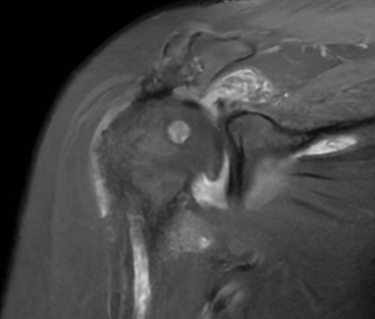

👉 En las imágenes de resonancia magnética se observa la ausencia o retracción severa de los tendones del manguito rotador, lo que impide una reparación convencional.